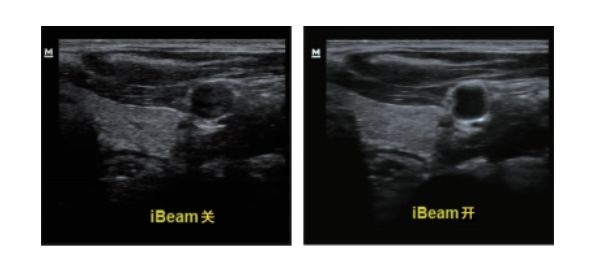

设备型号DP-50 全自动便携式超声诊断系统(迈瑞),该设备为DP 系列超声的较高级版本,具有iTouch 图像一键优化、 iBeam 复合成像、iClear 斑点噪声抑制、宽带频移谐波等技术。

iBeam复合成像: